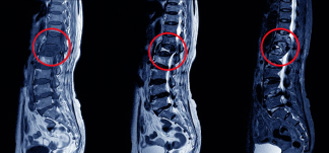

TB in spine. Pictures were taken from the internet. Link is: https://www.orthobullets.com/spine/2027/spinal-tuberculosis

Symptoms of TB disease in other parts of the body depend on the area affected (growing nodes, bone pain, abdomen pain, fistula etc.)

X-rays, CT scans or MRIs may be necessary to detect TB in organs other than the lungs.

According to the World Health Organization"s most recent TB report, extrapulmonary TB accounted for 14% of TB cases recorded globally in 2017. Unlike pulmonary TB, which is spread through the air from person to person – extrapulmonary TB is not infectious. A key risk factor for developing extrapulmonary TB is a compromised immune system which is why it is more common in patients infected with HIV. It can also occur in people with diabetes, cancer, low body weight and chronic kidney disease. Smoking and the use of drugs that can suppress the immune system also increase the risk of extrapulmonary TB. If defense mechanism fails, the bacteria multiply and cause disease in that specific organ system.